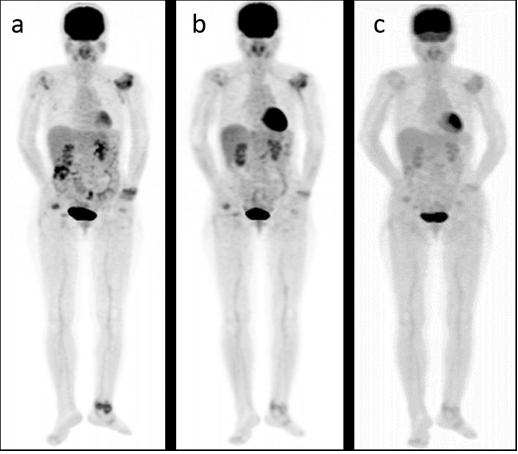

Positron emission tomography (PET)

nuclear medicine study that uses injectable radiotracer with a scan to evaluate function (blood flow, O2 use, glucose metabolism) visualizing uptake of radiotracer and look for metastasis

-assesses ischemic areas of heart

-used in neurology to evaluate tumors, seizure